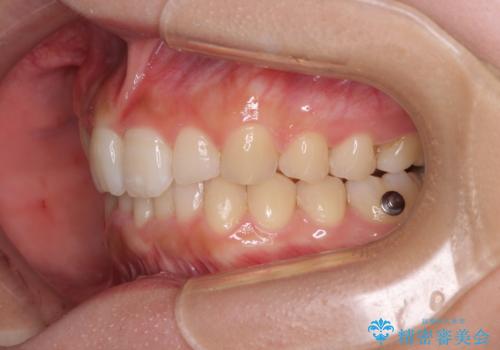

- 上顎の重なっている前歯を気にして来院された患者様です。

八重歯改善には抜歯が必要で、八重歯の移動量が多く、更には右側にずれている正中を改善する必要がありました。

インビザライン単体での治療は困難と判断し、補助装置により八重歯移動後にインビザラインを用いることとしました。